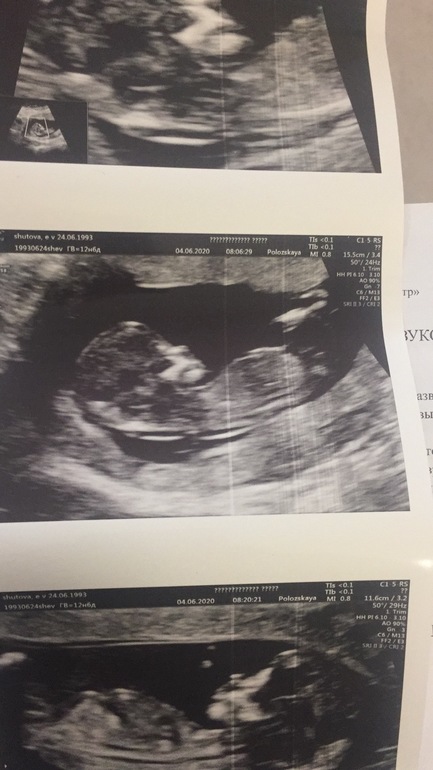

1 скрининг

Изменения и болезни во время БВсе, я прошла первый скрининг с кровью как положено))

Все отлично, малышка развивается.

Пол эта врач не предположила. Но по половому бугорку уже думаю все понятно) А что думаете вы?